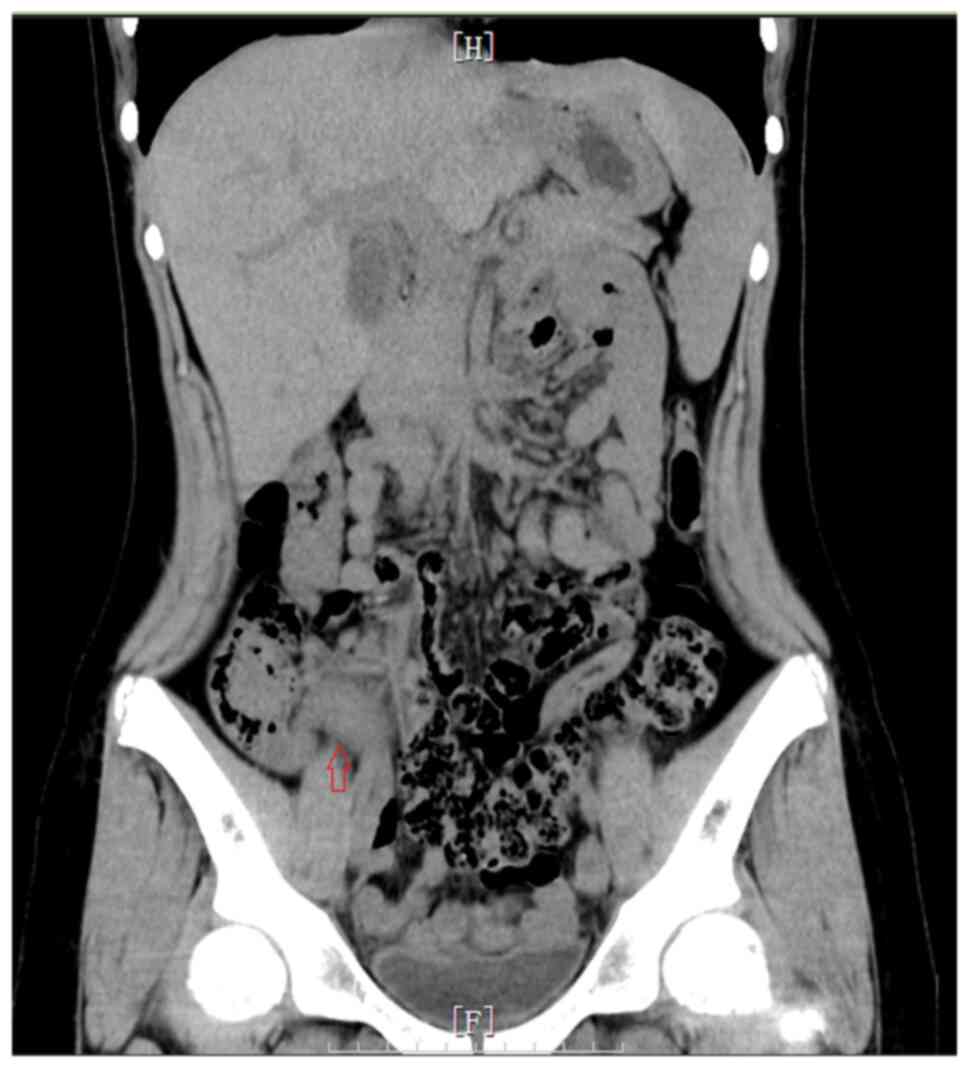

Figure 2

Computerized tomography (CT) scanning showing that the appendix is thickened with exudation, as indicated by the arrow.

A 13-year-old female adolescent individual with pain in the lower right abdomen for 3 days was first admitted to Shanghai Children's Hospital (Shanghai, China). She initially complained of pain in the lower right abdomen but without fever or diarrhea 3 days before admission. However, she vomited once 1 day before admission. No similar type of abdominal pain was experienced by the patient in the past. Physical examination revealed a fixed area of tenderness in the lower right abdomen without rebound tenderness. No obvious masses could be found in the abdominal area and the bowel sound was normal. Laboratory examination revealed her inflammatory markers to be elevated. Specifically, the white blood cell count was 8.49x109 cells/l and C reactive protein (CRP) count was 15 mg/l. The blood biochemical parameters of liver function, renal function and electrolytes were normal. In addition, abdominal ultrasound revealed that the diameter of the appendix was 9 mm, suggesting an acutely inflamed appendix (Fig. 1). From the computerized tomography (CT) scan images it could be observed that the appendix was thickened with exudation, where there was a small quantity of fluid within the pelvic cavity (Fig. 2).